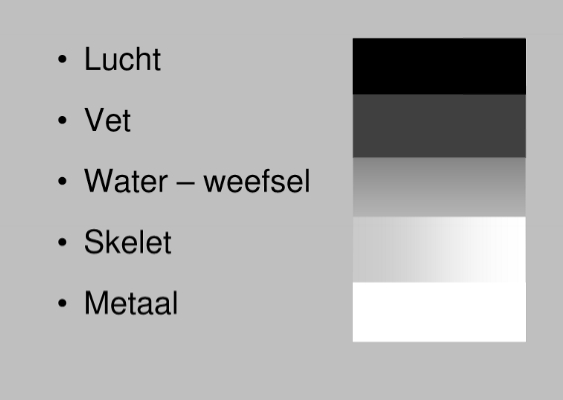

Principes van Radiografie

quadriceps-pees

redelijk dense structuur → absorbeert een beetje röntgenstralen (grijs)

patellapees = ligamentum patellae

vetweefsel

absorbeert niet veel röntgenstralen

stukje metaal

absorbeert veel röntgenstralen

bloedvaten, spieren

niet te onderscheiden van elkaar